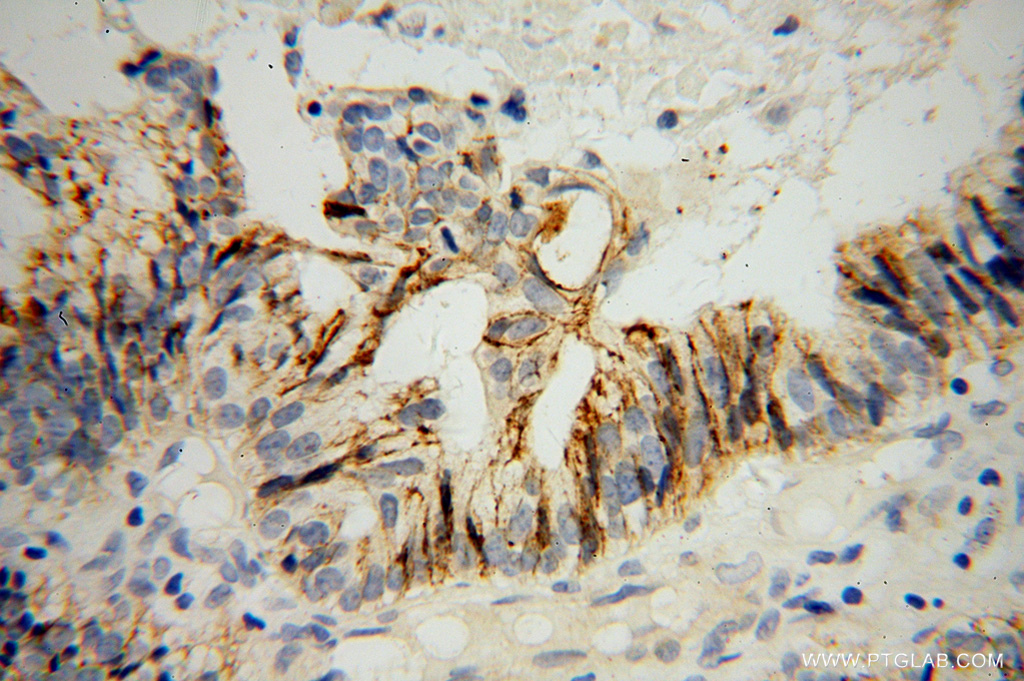

| Positive IHC detected in | human tonsillitis tissue, human ovary tumor tissue Note: suggested antigen retrieval with TE buffer pH 9.0; (*) Alternatively, antigen retrieval may be performed with citrate buffer pH 6.0 |

| Immunohistochemistry (IHC) | IHC : 1:800-1:3200 |

10593-1-AP targets CD138/Syndecan-1 in WB, IHC, IF, IP, CoIP, ELISA applications and shows reactivity with human, mouse samples.

CD138, also named as Syndecan-1 (SDC1), is an integral membrane protein. It participates in cell proliferation, cell migration and cell-matrix interactions via its receptor for extracellular matrix proteins. It is a heparan sulfate proteoglycan expressed on the surface of, and actively shed by, myeloma cells. Altered syndecan-1 expression has been detected in several different tumor types. CD138 was regarded as a useful marker for labeling normal and neoplastic plasma cells and plasmacytoid lymphomas. CD138 has a calculated molecular weight of 32.5 kDa, the apparent molecular weight is higher due to extensive glycosylation.